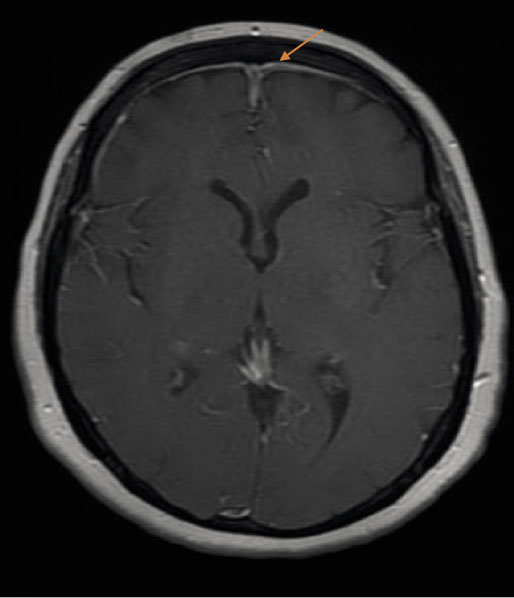

Her complete blood count revealed a hemoglobin of 14.8 g/dL, total white cell count of 9850 /µl, and a platelet count of 408,000 /µl. The erythrocyte sedimentation rate was elevated at 85 mm/hr (normal range 0-30 mm/hr in women over 50). C-reactive protein was 7.3 mg/L. Blood chemistry levels were within normal limits. Urinalysis was normal with no proteinuria or casts. Autoimmune workup was done due to the presence of elevated inflammatory markers. Antinuclear antibody and anti dsDNA were negative. Serum C3 and C4 levels were low. She had a positive rheumatoid factor of 32 IU/ml (normal <15) and positive proteinase 3 antinuclear cytoplasmic antibody (PR-3 ANCA) at >8 AI (normal <1). Anti-myeloperoxidase antibodies were negative. Her chest x-ray was within normal limits. Computed tomography (CT) of the head and sinuses demonstrated bilateral maxillary, ethmoid, and sphenoid sinus opacification without bony erosions. CT angiography of the head and neck was normal. Cerebral magnetic resonance imaging with gadolinium (MRI) showed asymmetric enlargement of the infraorbital and canalicular portion of the right optic nerve suggestive of optic neuritis (Figure 1). No intraparenchymal abnormalities or evidence of venous sinus thrombosis were detected. She had significant meningeal thickening and enhancement in the frontal region that represented pachymeningitis (Figure 2). The patient refused to undergo a lumbar puncture for cerebral spinal fluid studies.

Figure 1

Figure 1. Cerebral magnetic resonance imaging with gadolinium (MRI) showing asymmetric enlargement of the infraorbital and canalicular portion of the right optic nerve suggestive of optic neuritis.